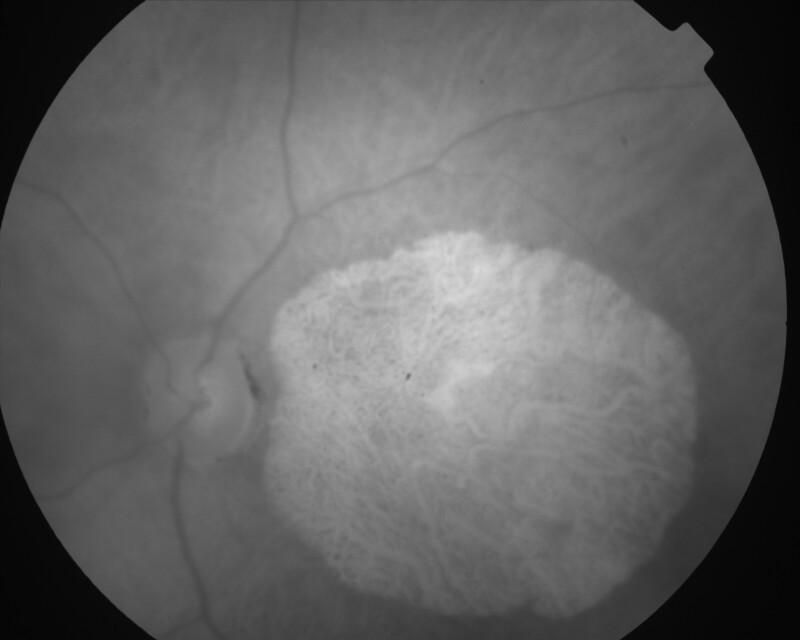

CICATRICE APRES EXERESE CHIRURGICALE DE NEOVAISSEAUX

IM000014.jpg